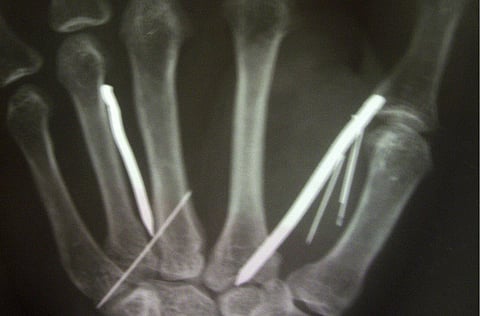

Surgeons at Sri Lanka's southern Kamburupitiya hospital removed 19 out of a total of 24 nails - some two-inches long - and a needle that were in her arms, legs and forehead during a three-hour operation.

"She said her employer heated the nails and then hammered them into her body," Gajadeera told AFP. "The nails were in her arms, legs and forehead."

Surgeons at the hospital removed 13 big nails, each two-inches long, and six smaller ones, Gajadeera said.

He said the remaining nails were not immediately removed because the procedure might have resulted in serious nerve damage.